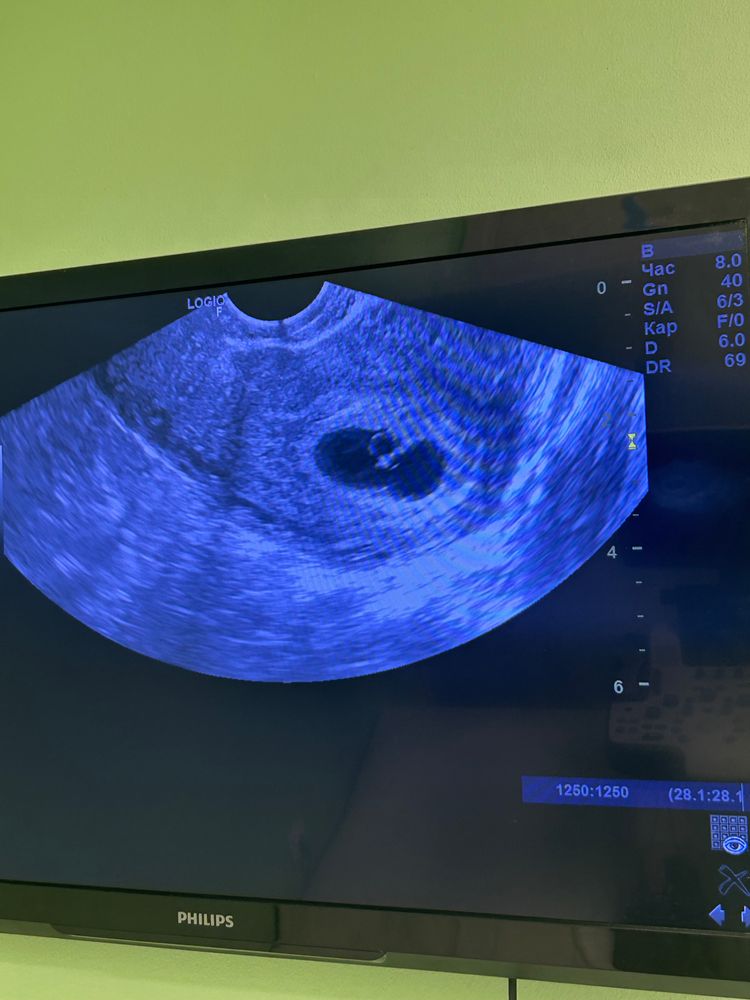

моя ситуация такая. Первое узи было в 4н6д сделали узи, нашли 1 плодное яйцо, 1 желточный мешочек, эмбрион не визуализировали. Второе узи в 5н4д нашли 2 плодных яйца, 1 желточный мешочек, 1 желтое тело, у 1 эмбриона было видно, как бьется сердечко, не слушали и рядом как бы просматривается еще один.

У вас в заключении написано, что визуализируются 2 эмбриона и обоих есть сердцебиение. ЖМ один, это странно, скорее всего второй просто не увидели, что-то перекрывает. На повторном узи ждать замеры чсс🤭😉